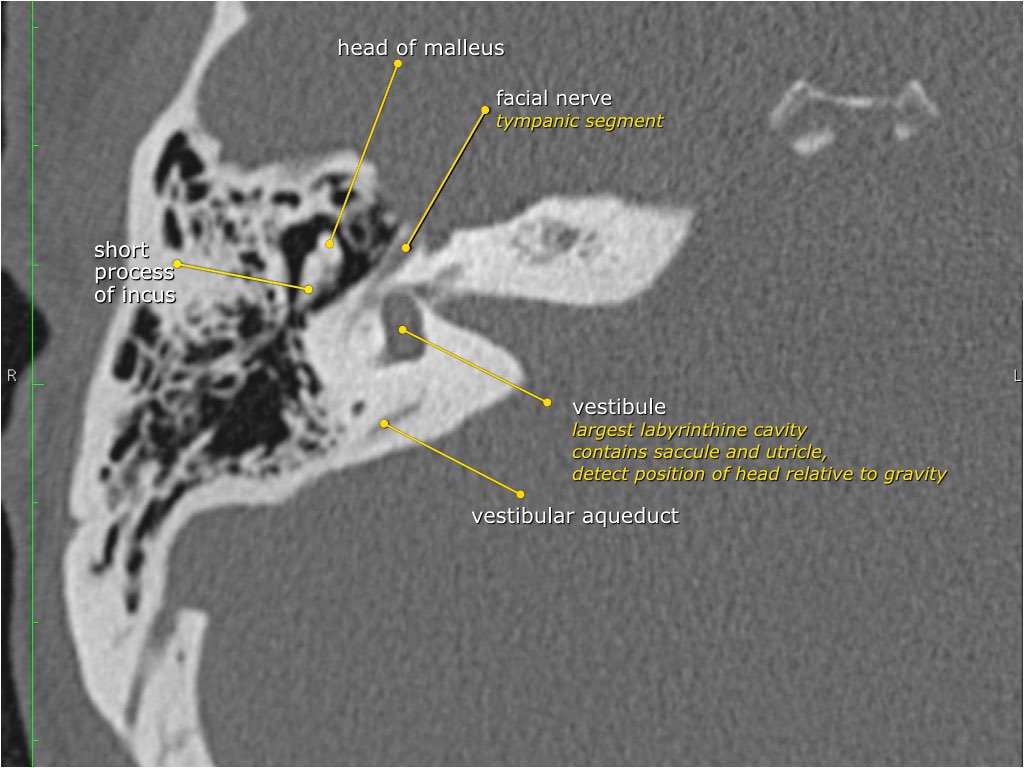

Dây thần kinh mặt

Đoạn mê nhĩ của dây thần kinh mặt xuất phát từ ống tai trong, chạy gần như vuông góc với trục dài của xương đá, gập góc nhọn về phía trước để đến hạch gối (geniculate ganglion).

Tại hạch gối, dây thần kinh mặt tạo thành một khúc quặt hình chữ U (genu thứ nhất của dây thần kinh mặt) để chạy ra phía sau theo đoạn nhĩ dọc theo thành trong của thượng nhĩ.

Hang bào chũm (Antrum)

Hang bào chũm là một tế bào khí lớn nằm phía trên và phía sau hòm nhĩ, thông với hòm nhĩ qua ngách hang (aditus ad antrum).